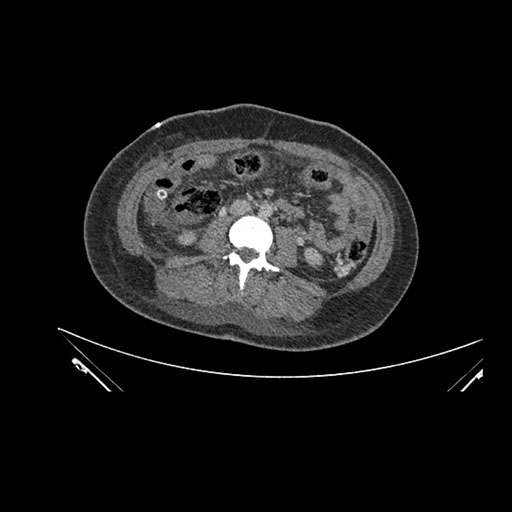

Imaging Analysis

Look through the patient's CT scan to identify any areas of concern for the necessary procedure.

Coronal Arterial

Based on initial findings, which issue(s) would you be most concerned about?